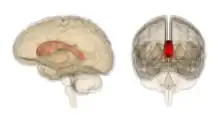

Sagittal section of brain, front part to the left. The corpus callosum can be seen in the center, in light gray